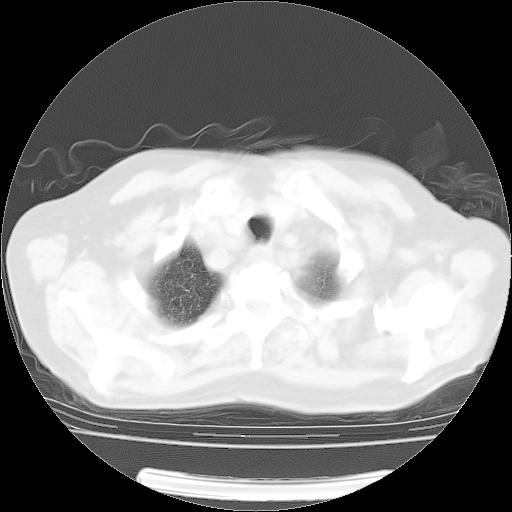

4月14日肺部CT